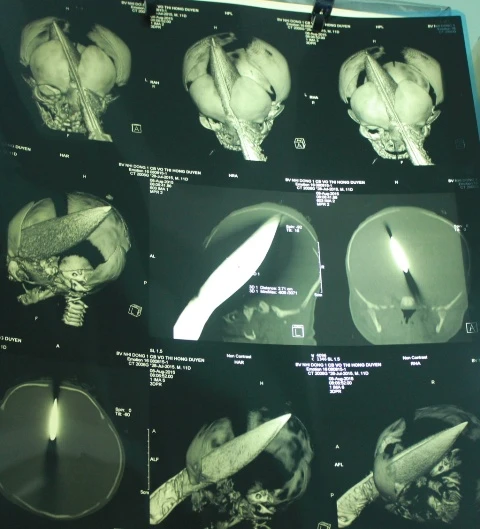

Kết quả chụp CT cho thấy, vết thương từ hốc mắt trái xuyên qua não phải, thấu ra phía sau với chiều dài 11 cm. Các BS BV Nhi đồng 1 kết hợp hội chẩn với BS ngoại thần kinh BV 115, đánh giá bệnh nhi có thể đột tử bất cứ lúc nào do vết thương kèm tiền sử bệnh viêm phổi. Ngay sau đó bệnh nhi được đẩy vào phòng mổ cấp cứu, mở hộp sọ, sau hơn ba giờ, các BS đã lấy con dao ra khỏi đầu bệnh nhi.

BS Đào Trung Hiếu, Phó Giám đốc BV Nhi Đồng 1, cho biết sau mổ bệnh nhi được theo dõi chặt trong vòng 24 giờ tới vì có thể xảy ra hiện tượng chảy máu, vấn đề nhiễm trùng,… Những tổn thương ở vùng mắt chưa có dấu hiệu gì bất thường, tay chân bé vẫn cử động được. Sau khi bé ổn định, BV sẽ được chụp CT để đánh giá lại tổn thương não. Riêng con dao lấy ra là loại dao bầu, dài 28 cm, ngang 2,7 cm. Phần dao đâm vào đầu khoảng 11cm.